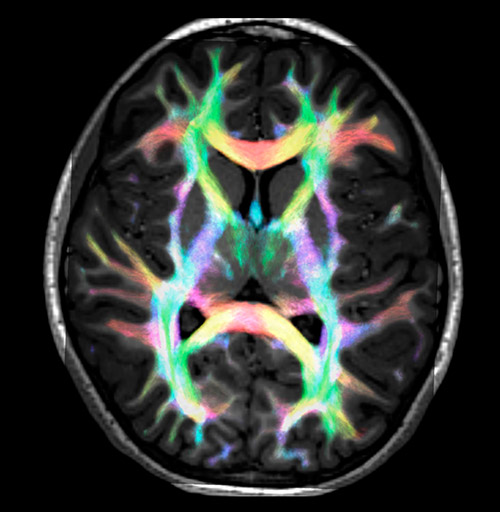

Fiber tracking from the left and right hippocampi to the fornix.

Fiber tracking from the left and right hippocampi to the fornix (green), and the corticospinal track based on a seed region of the posterior limb of the internal capsule.